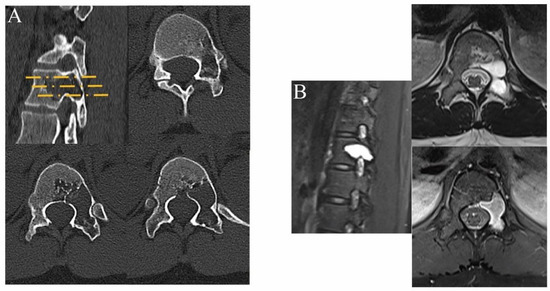

2. Materials and Methods

2.1. Preoperative Preparations

2.2. Surgical Technique

3. Results